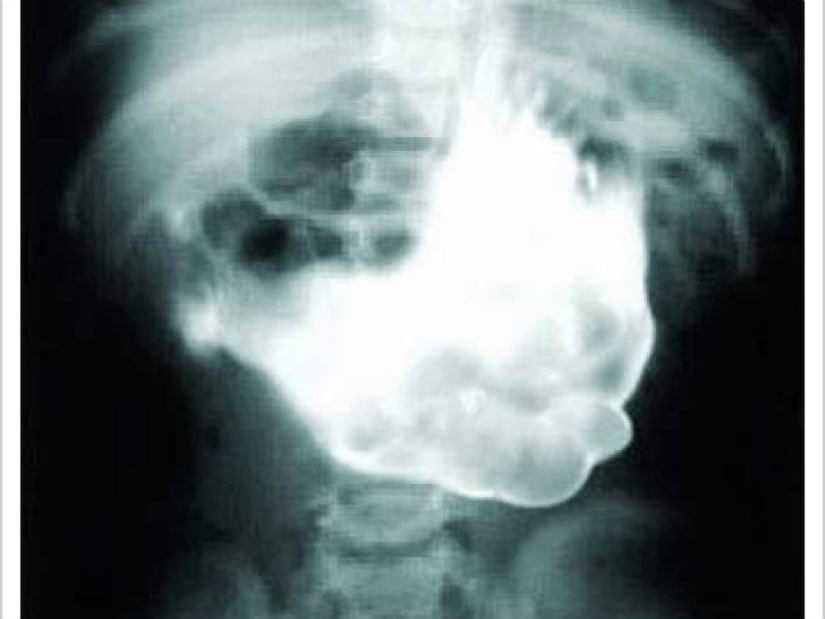

Te lo advertimos, no mires si acabas de sentarte a almorzar. Una vez, a una niña de 18 años se le quitó un trozo de lana que pesaba 4,5 kg del estómago.